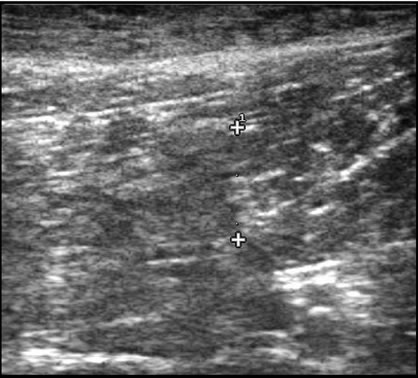

Cris, a four-year-old male German shepherd police dog, became suddenly lame while training. Five days later, the owner reported that the dog’s lameness had improved but that the dog’s gait remained abnormal. Cris presented at that time bearing less weight on the left rear limb with a slight circumduction gait. On palpation, the distal two-thirds of the left semitendinosus muscle was swollen at the mid belly region with a palpable dimple. Sonography revealed poorly defined hypoechoic region in the distal two-thirds of the left semitendinosus muscle 8.1 mm wide × 30.8 mm long. These findings are compatible with a focal tear in the left semitendinosus muscle with an area of central hemorrhage and/or edema consistent with a grade 3 tear (Figure 1). No abnormalities were seen in the right semitendinosus muscle. At that time, the surgeon prescribed Previcox (227 mg 5 days/ week) and antioxidant therapy (Niacinamide, 50 mg/day; Sam-E, 225 mg/day; Vitamin E, 200 IU/day; 3V Caps, 1 cap/day; and Omega Mint, 1/day) and the dog was prescribed cage rest for two weeks.

Figure 1. (a) Ultrasound scan of Cris left ST muscle tear before treatment: An 8 mm wide and 30 mm long poorly defined hypoechoic area is noted in the distal two thirds of the ST muscle compatible with a muscle tear; (b) Cris 82 days after treatment: The lesion is poorly defined with an iso-echoic area that measured 11 mm wide and 15 mm in length. An increase in fiber numbers is noted that are oriented in the same plane as the normal muscle.